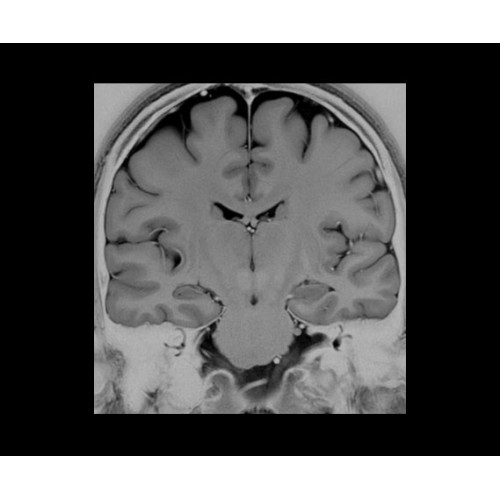

• Специальный пакет приложений для измерения и сравнения объемных изображений ЦНС с нормами поможет вам в диагностике нейродегенеративных заболеваний, а дополнительные инструменты визуализации — в постановке точного диагноза с помощью бета-амилоидов и радиоизотопных маркеров ФДГ.

SIGNA PET/MR 3.0T — это гибридная система, в которой совмещаются две принципиально разные технологии — магнитно-резонансную томографию (МРТ) и позитронно-эмиссионную томографию (ПЭТ). Система отличающийся высокой чувствительностью и эффективностью и предназначена для диагностики в области онкологии, неврологии, кардио-васкулярных исследований, исследований воспалительных процессов.

Компания GE Healthcare представляет революционную, полностью интегрированную систему SIGNA PET/MR1, в которой сочетаются времяпролетная технология (TOF) и возможности напряженности магнитного поля 3.0 Тл. Мы поможем вам поднять исследования на более высокий уровень. SIGNA PET/MR позволяет достичь впечатляющей точности и скорости исследований, а благодаря новейшей технологии реконструкции Q.Clear2 качество изображений улучшается в два раза. Кроме того, в систему включен полный набор клинических приложений и гибких катушек для проведения любых видов исследования, открывая для вас возможности визуализации, о которых вы даже не догадывались.